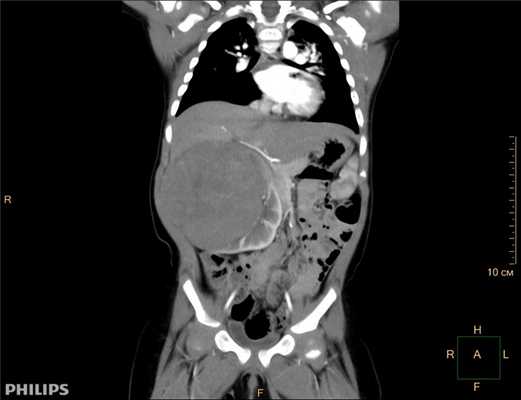

- Компьютерная томография органов брюшной полости и забрюшинного пространства с оральным и внутривенным контрастированием.

- Магнитно-резонансная томография брюшной полости и забрюшинного пространства без и с контрастным усилением (даёт дополнительную информацию о распространённости и связи опухоли с окружающими органами).

Опухоль Вильмса. Компьютерная томография